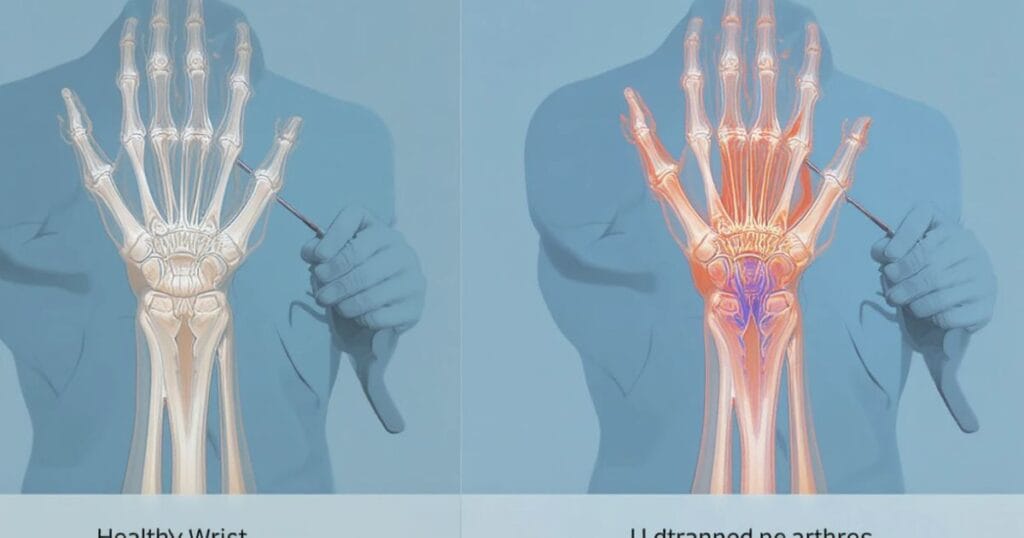

When you sustain a motor vehicle accident injury to the wrist, the intricate anatomy makes the region vulnerable. Bones such as the radius and ulna, small carpal bones, tendons and the median nerve are all at risk. The result: hand and wrist trauma that affects grip strength, flexibility, even your job.

In cases where the wrist absorbs sudden hyper-extension or jolt during a crash, you may face injuries worse than you anticipate. Harsh forces can produce a wrist ligament injury from accident or trigger carpal tunnel after car crash because of swelling compressing the median nerve. Understanding that injury potential helps you prepare for both medical and legal steps.

High-impact collisions frequently cause several types of wrist injuries. A wrist fracture car accident happens when a bone snaps under stress, sometimes requiring plates or screws for repair. Next, car accident soft tissue injury like ligament tears, tendon ruptures or contusions can severely affect wrist stability and movement. Additionally, hand injury car accident may involve the wrist joint in dislocation or misalignment events.

It is critical to recognise that even injuries which seem superficial—such as bruising or swelling—can hide deeper problems like nerve damage in wrist after collision. Without proper diagnosis and treatment, you risk persistent pain, reduced function, or even disability.

Diagnosis of a wrist injury after a crash starts with a physical exam and collection of medical documentation including your description of how the event happened. Imaging tools like X-rays and MRI scans (medical diagnostic entities) provide insight into bone fractures, ligament tears or soft tissue damage.